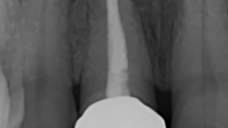

The main issue involved the upper right central incisor (tooth 1.1), which was devitalized and presented recurrent abscesses. Clinical and radiographic evaluation confirmed the presence of buccal bone wall resorption, leading to a significant defect in the alveolar ridge. This condition compromised both the hard tissue and the surrounding soft tissue, posing a challenge for achieving long-term stability and esthetic success in the anterior maxilla.

The surgical protocol began with the atraumatic extraction of tooth 1.1 to preserve as much of the alveolar socket as possible. Immediately following extraction, an N1 implant was placed into the socket using a guided surgical approach to ensure ideal three-dimensional positioning. The “one abutment one time” technique was applied to minimize soft tissue manipulation during the healing phase, which is particularly important in esthetic areas.

Given the significant buccal defect, guided bone regeneration (GBR) was performed simultaneously. A mixture of autologous bone and creos™ xenogain™ was applied to the defect and covered with a resorbable creos™ membrane to restore ridge width and support the buccal contour. In addition, a connective tissue graft was harvested and placed in the vestibular region to increase the thickness of keratinized mucosa. This combined approach addressed both hard and soft tissue deficiencies, providing the biological foundation for a stable and esthetic outcome.